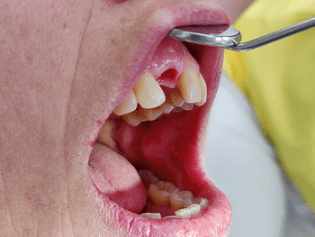

Nach Notdienst-Behandlung: Ästhetisches Ergebnis dank umfangreicher Vorbehandlung und Planung – von Daniel Liss, AllDent Zahnzentrum Leipzig

In diesem Fall hätte eine Brückenversorgung in regio 11 viel gesunde Zahnhartsubstanz gekostet. Daher fiel die Entscheidung der Patientin auf eine Implantatkrone. Neben des wiederholten Bruchs der Interimsprothese aufgrund des Tiefbisses stellte die provisorische Versorgung aufgrund der Lage im Frontzahnbereich hohe Anforderungen. Die Patientin verfügt überdies über eine hohe Lachlinie, bei der die Gingiva komplett sichtbar ist. Um den ästhetischen Ansprüchen gerecht zu werden, war eine gründliche Planung und längerer Vorlauf erforderlich. Das Ziel war nicht nur, ein ästhetisch befriedigendes Ergebnis zu liefern, sondern dieses auch langfristig zu erhalten. Deswegen dauerte die Vorbehandlung mit Socket Preservation, PA-Behandlung, Augmentation, Implantation und Gingivaformung durch die provisorische Krone insgesamt neun Monate.

Die Patientin zeigte sich mit dem Ergebnis jedenfalls hochzufrieden und lobte besonders die interdisziplinäre Zusammenarbeit zwischen behandelndem Zahnarzt Daniel Liss, Oberärztin Dr. Yun-Chie Roh, Chirurgin Dr. Irene Göllnitz und dem Zahntechniker Philip Janz.